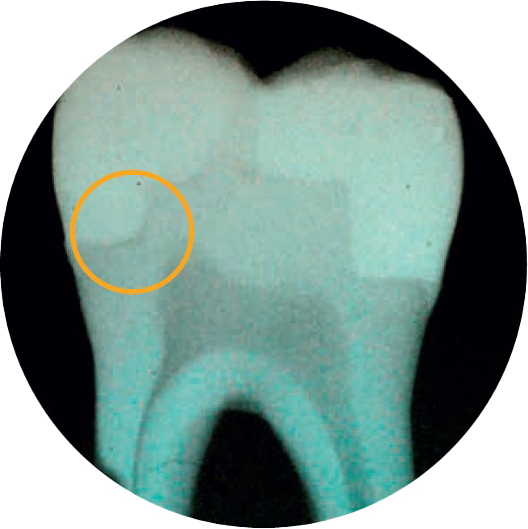

Un doute quant à la formation de vides ?

2 dentistes sur 3 indiquent que l’adaptation de la cavité est l’aspect le plus important d’une restauration réussie.4